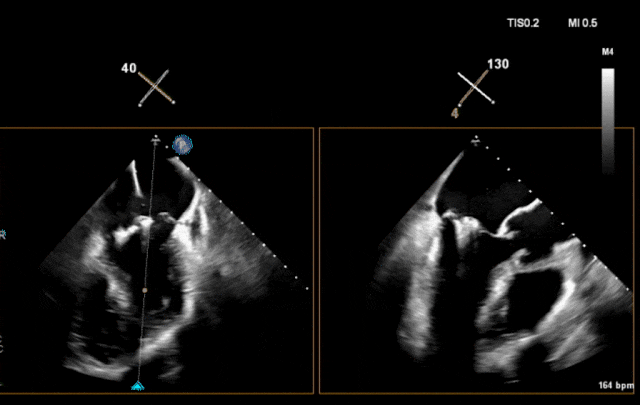

心脏超声示左室增大,二尖瓣2、3区脱垂伴重度反流(腱索断裂),Carpentier分型Ⅱ型,典型Barlow综合征表现;二尖瓣开放面积5.0cm²,3区瓣环内径31mm,前叶长22mm、后叶17mm,前叶收缩期关闭瓣体部分呈拱形突向左房腔,瓣膜游离缘对合欠佳,可见腱索断裂,长度9mm;2区瓣环内径32mm,前叶长22mm、后叶10mm,前后叶均可脱垂;三尖瓣重度反流。CDFI示瓣口重度偏心性反流,反流束沿主动脉后壁走行,肺静脉收缩期可见反向频谱。

术前超声

图片

术前瓣叶

术前反流